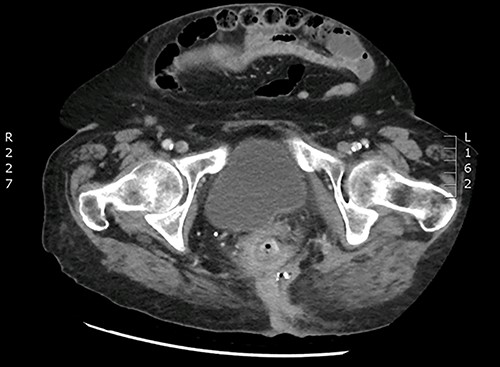

A 90-year-old woman presented with abdominal pain and pneumaturia; in her medical history we find a laparotomy mesh rectopexy 15 years ago. CT scan showed inflammation around the mesh that can also be seen entering the bladder (Figs 5 and 6).

While cystoscopy showed the presence of the mesh in the urinary bladder, rectoscopy visualized the mesh on the anterior wall of the rectum at 3 cm from the anal marge.